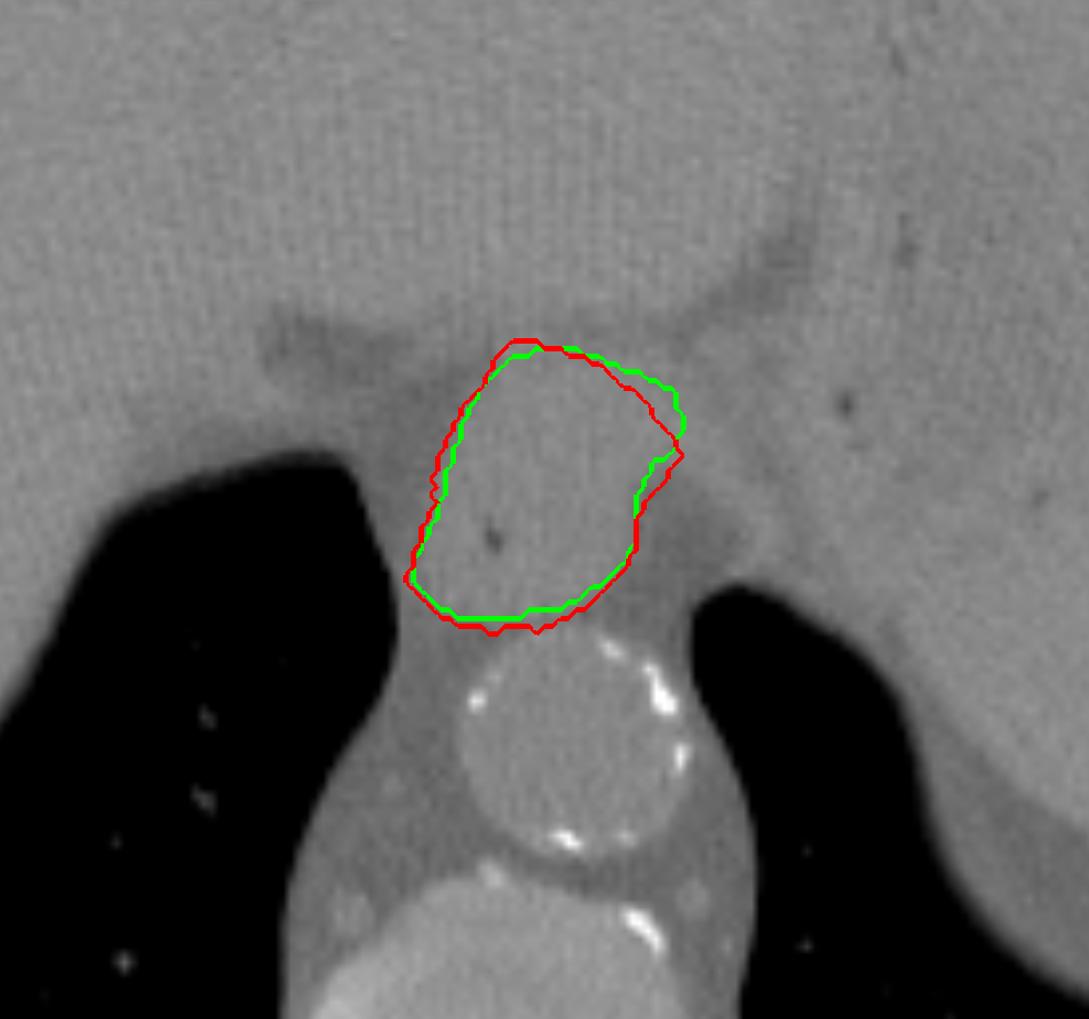

Visual results of our algorithm compared to the reference contour for 6 cases in axial and sagittal view are depicted in Fig. 5. From the sagittal views it can be observed that manual contours are not as smooth as the automatic contours, which could be due to the breathing artifacts. The use of convolutions and post-processing in 3D aids at processing information of the 3D context through several slices, which is reflected in the smoother automatic contours shown in these images. On the other hand, from the axial views we can realize that, despite of the similarity with respect to neighboring tissues, and heterogeneity of the inner region of the esophagus, our automatic system provides contours that are comparable with the reference standard.

Refer to caption a) clinical case 09 sagittal view Refer to caption b) clinical case 13 sagittal view Refer to caption c) clinical case 20 sagittal view

Refer to caption d) clinical case 09 axial view Refer to caption e) clinical case 13 axial view Refer to caption f) clinical case 20 axial view

Refer to caption g) public case 01 sagittal view Refer to caption h) public case 12 sagittal view Refer to caption i) public case 24 sagittal view

Refer to caption j) public case 01 axial view Refer to caption k) public case 12 axial view Refer to caption l) public case 24 axial view

Figure 5: Contouring results for 6 cases in different views. The green line indicates the reference standard, the red line depicts the contour generated by the proposed algorithm.